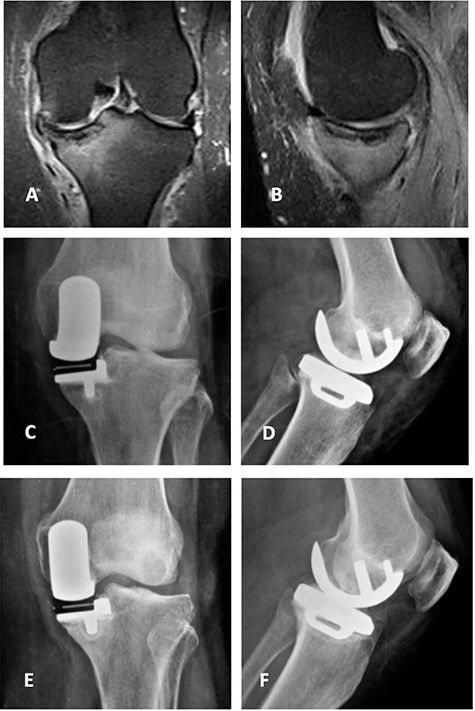

Coronal (A) and sagittal (B) T2 MRI—left knee—showing severe MP SIFK; Anterior (C) and lateral view (D) X-ray images of immediate postoperative period (medial UKA); Anterior (E) and lateral view (F) X-ray images with 3 months of follow-up with tibial component loosening.